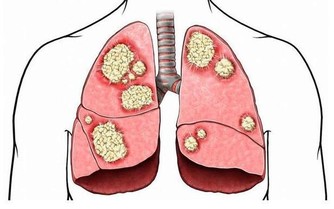

很多人,或許有個疑問,那就是,戒菸後肺部真的還能恢復健康嗎?

專家表示,戒菸後肺部是可以慢慢恢復的。若在35歲前成功戒菸,你的預期壽命會同常人一樣。

戒菸24小時後: 血液系統、血壓及心臟健康等會逐漸恢復正常。

戒菸48小時後: 消除大部分尼古丁,嗅覺與味覺也逐漸變更好。

戒菸3~9個月後:呼吸問題變好了,肺部開始逐漸恢復健康。

戒菸1年以後:冠狀動脈疾病風險降低50%

戒菸5年後:中風的風險降低至和不抽煙的人同樣水平。

戒菸10年後:患肺癌的機率達到了正常吸煙人的一半。

戒菸15年後:患冠心病的風險同不抽煙的人一樣。死亡的風險也恢復到了和不抽煙人一樣。

所以,任何時候戒菸都不晚,為了自己和家人的健康,嘗試著努力戒菸吧~